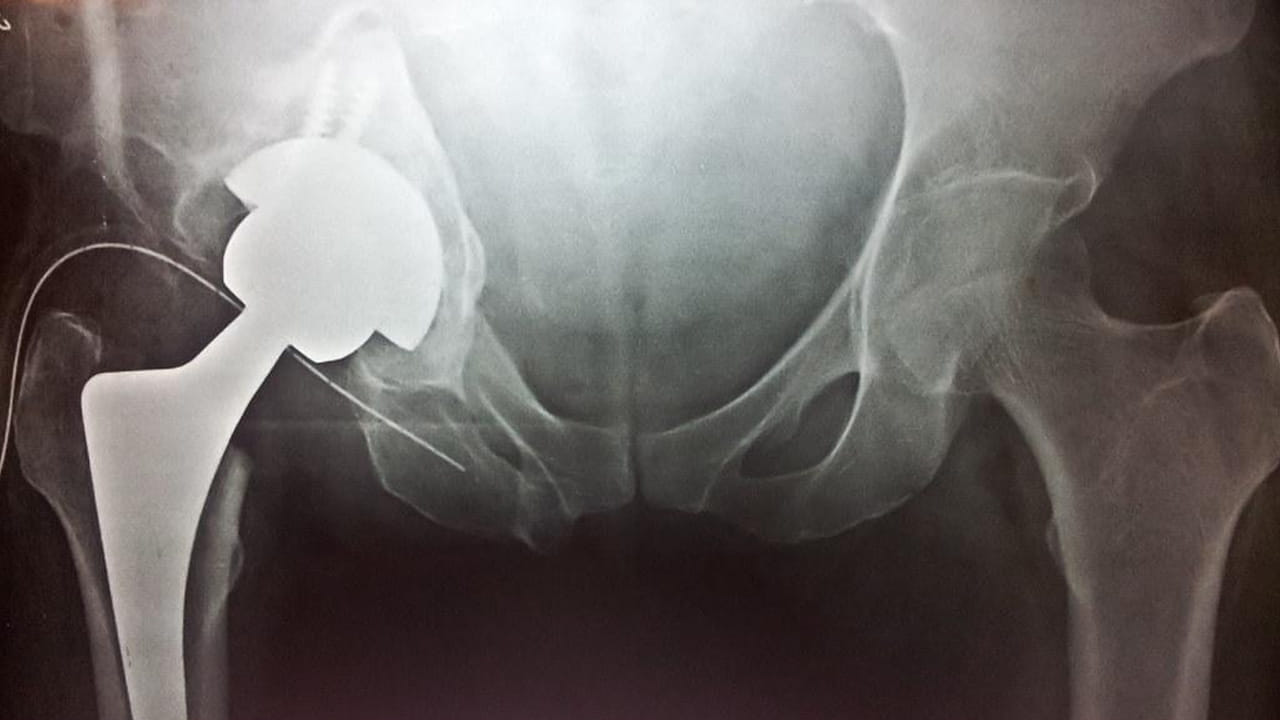

మన శరీర నిర్మాణంలో ఎముకల పాత్ర ఎంతో కీలకం. అయితే వయసు పెరిగే కొద్దీ ఎముకల సాంద్రత క్షీణిస్తుంది. దీనికి తోడు ఒత్తిడి, ఆరోగ్యకరమైన జీవనశైలి, వివిధ రకాల వ్యాధులు మనిషి ఎముకల ఆరోగ్యంపై తీవ్ర ప్రతికూల ప్రభావం చూపిస్తాయి. కాగా ఎముకల ఆరోగ్యంపై అమెరికాలోని టెక్సాస్ వేదికగా అమెరికన్ సొసైటీ ఆఫ్ బోన్ అండ్ మినరల్ రీసెర్చ్ ఆధ్వర్యంలో ఓ కీలక సమావేశం నిర్వహించారు. యూనివర్సిటీ ఆఫ్ హాంకాంగ్లో ఫార్మకాలజీ అండ్ ఫార్మసీ విభాగంలో అసోసియేట్ ప్రొఫెసర్గా పని చేస్తోన్న చింగ్-లంగ్ చియుంగ్ ఈ సమావేశంలో పాల్గొని ఎముకల వ్యాధులకు సంబంధించి పలు షాకింగ్ విషయాలు బయటపెట్టారు. రోజురోజుకు ఆస్టియోపోరోసిస్ బాధితుల సంఖ్య పెరుగుతుందని, 2050 నాటికి హిప్ ఫ్రాక్చర్ల సంఖ్య రెట్టింపు అవుతుందని, ఇది తమ అధ్యయనంలో తేలిందని పేర్కొన్నాడు.

కాగా 2005 – 2018 సంవత్సరాల మధ్య సుమారు 19 దేశాల్లో 50 ఏళ్లకు పైగా వయసు ఉండి తుంటి పగుళ్లతో సతమతమైన వివరాలను సేకరించి ఈ అధ్యయనం నిర్వహించారు. ఈ దేశాల్లో తుంటి పగుళ్ల కేసులు గణనీయంగా పెరుగుతున్నాయని ఈ అధ్యయనంలో తేలింది. ప్రపంచ బ్యాంక్ గణంకాల ప్రకారం 2030 – 2050 నాటికి హిప్ ఫ్రాక్చర్ బాధితులు భారీగా పెరుగుతారట. 2018తో పోలిస్తే ఈ సంఖ్య రెండింతలు పెరిగే అవకాశం ఉందట. మరో ముఖ్యమైన విషయమేమిటంటే.. మహిళల్లో కంటే పురుషుల్లో ఈ సమస్యలు ఎక్కువగా ఉన్నాయని ఈ అధ్యయనంలో తేలింది. ప్రపంచ ఆరోగ్య సంస్థ ప్రమాణాల ప్రకారం హిప్ ఫ్రాక్చర్ ప్రమాదం 50- 84 సంవత్సరాల మధ్య వయస్సు గల మహిళల్లో 21.2 శాతం ఉందని, పురుషుల్లో 6.3 శాతం ఉన్నట్లు కనుగొన్నారు.

కాగా ఇదే విషయంపై ఫరీదాబాద్లోని ఫోర్టిస్ ఎస్కార్ట్స్ హాస్పిటల్ ఆర్థోపెడిక్స్ అదనపు డైరెక్టర్ డాక్టర్ హరీష్ ఘూటా స్పందించారు. గత దశాబ్ద కాలంగా భారతదేశంలో కూడా తుంటి పగుళ్ల బాధితుల సంఖ్య పెరుగుతుందని ఆయన తెలిపారు. ‘దేశంలో తుంటి పగుళ్ల కేసుల్లో గణనీయమైన పెరుగుదల కనిపిస్తోంది. దీనిక ప్రధాన కారణం.. బోలు ఎముకల వ్యాధి. క్యాల్షియం లోపంతో ఈ సమస్యలన్నీ తలెత్తుతున్నాయి. సాధారణంగా, బోలు ఎముకల వ్యాధి వయస్సుతో ముడిపడి ఉంటుంది. దీనికి తోడు శారీరక వ్యాయామం లేకపోవడం, అనారోగ్యకరమైన జీవనశైలి వల్ల ఆస్టియోపోరోసిస్ సమస్యలు తలెత్తుతున్నాయి. మనదేశంలో వృద్ధుల జనాభా చాలా ఎక్కువగా ఉంది. దీనికి తోడు ప్రజల్లో శారీరక శ్రమ లోపించింది. అయితే వైద్య రంగంలో పెరుగుతోన్న సాంకేతికతను ఉపయోగించుకుని ఎక్కువ మంది రోగులకు చికిత్స చేస్తున్నాం. బోలు ఎముకల వ్యాధితో బాధపడేవారిలో వెన్నెముక మాత్రమే కాకుండా తుంటి సమస్యలు కూడా ఎక్కువగా వెలుగు చూస్తున్నాయి. చాలా మంది మధుమేహ వ్యాధిగ్రస్తులు, ఊబకాయం ఉన్నవారు తక్కువ జీవక్రియ రేటును కలిగి ఉంటారు. శారీరక శ్రమ కలిగి ఉండరు. అలాంటి వారిలో కీళ్ల నొప్పులు, ఎముకల వ్యాధులు ఎక్కువగా ఉంటున్నాయి’ అని డాక్టర్ చెప్పుకొచ్చారు.